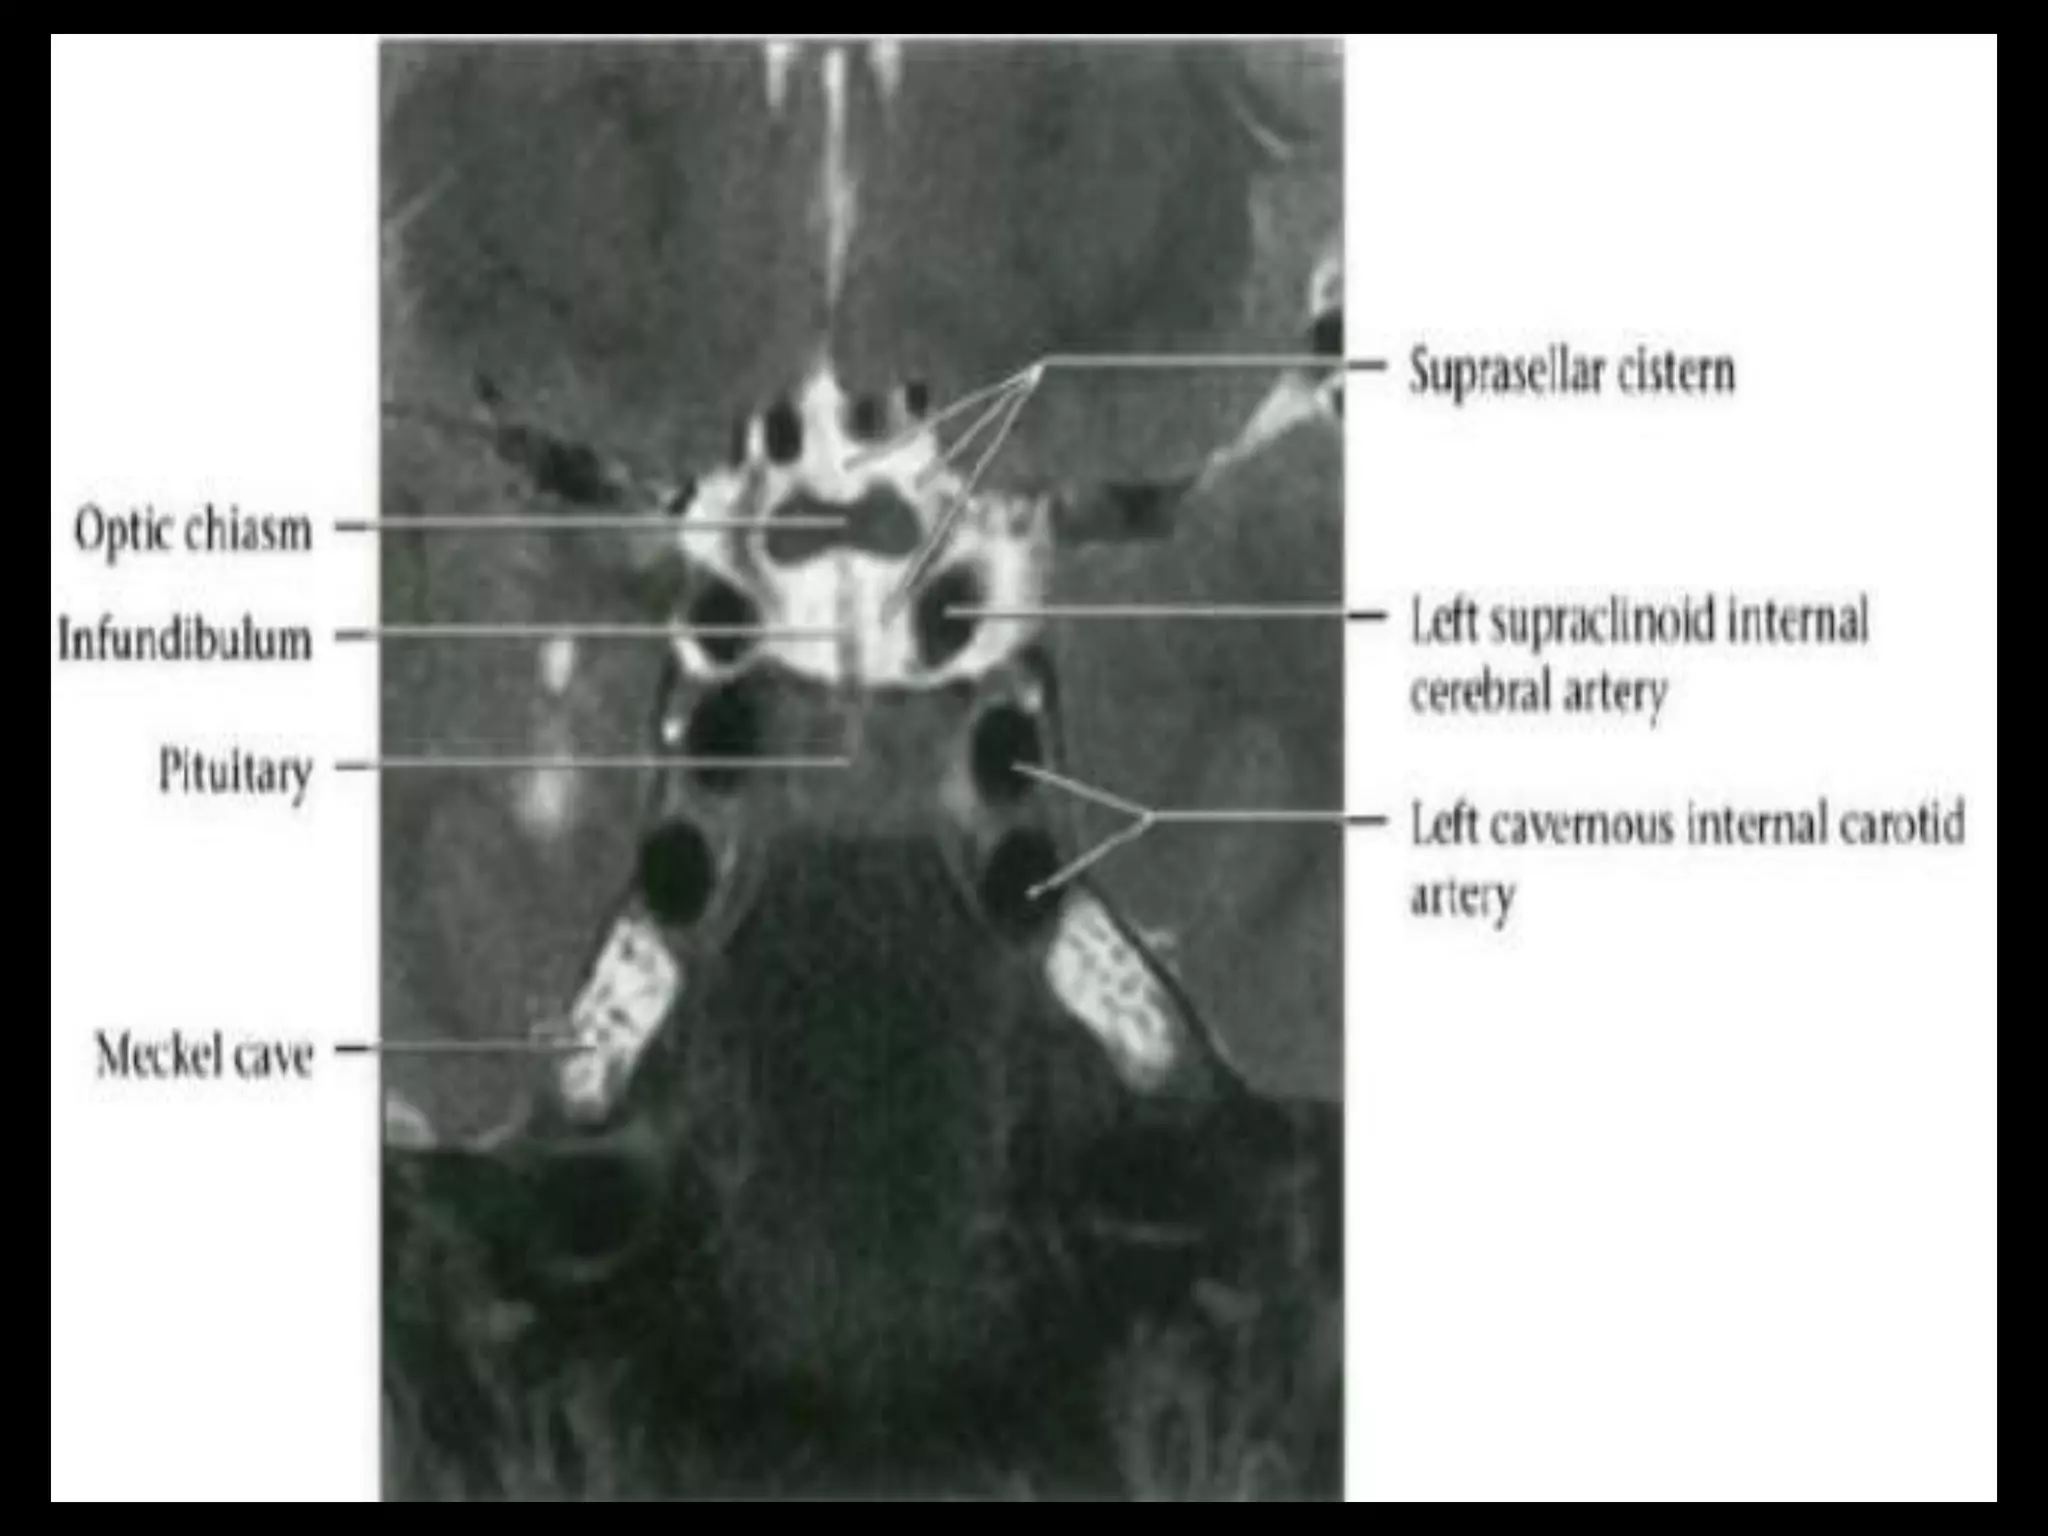

Suprasellar Cistern

And Optic Apparatus.

Suprasellar Cistern AndOptic Apparatus.